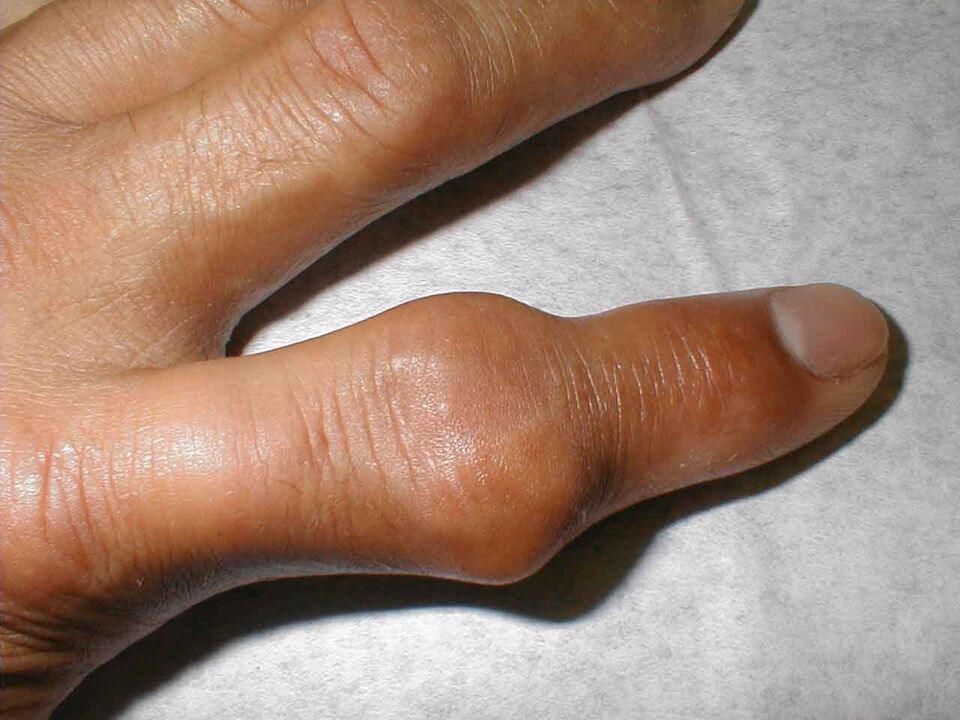

Les doigts gonflent et font mal même au repos. La douleur survient souvent la nuit. L'apparition de la maladie peut être aiguë, on observe une rougeur des articulations phalangiennes, elles sont chaudes et denses au toucher. La température de tout le corps peut augmenter.

L'arthrite ou l'inflammation des articulations des doigts peuvent survenir en raison de la pénétration de la flore bactérienne dans celles-ci. Il s'agit le plus souvent de staphylocoques ou de streptocoques. La bactérie provoque une inflammation aiguë caractérisée par un gonflement important des articulations, une rougeur et une augmentation de la température locale.

Le syndrome douloureux est prononcé. Le patient se plaint de contractions musculaires et de douleurs aiguës même au repos. Il est presque impossible de serrer les mains ; essayer de prendre quoi que ce soit s'accompagne de sensations douloureuses intenses.

Les articulations deviennent enflammées et, dans les cas avancés, se déforment tellement que les doigts perdent complètement leurs fonctions.

L’articulation grossit et devient rouge. Il est impossible de le toucher et les analgésiques n'aident pas beaucoup. Ce syndrome douloureux sévère est provoqué par l'accumulation de cristaux pointus de sels (urates) dans la cavité articulaire, qui s'enfoncent dans les tissus mous à chaque mouvement, les blessant.

La ligamentite sténosante commence à progresser à la suite d'une inflammation du ligament situé à la base de l'index. Au fur et à mesure que la maladie progresse, un « claquement » du doigt apparaît, lorsque la flexion est douloureuse et difficile, et que l'extension sans l'aide de la trotteuse devient quasiment impossible. A la base, à la place du ligament enflammé, on palpe une formation ronde dense. Dans ce cas, la douleur peut s’étendre à toute la main et irradier jusqu’au cou. Extérieurement, les doigts semblent bleuâtres et enflés.